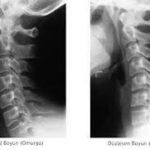

Boyun Düzleşmesi nedir?

Servikal Lordoz Nedir?

Servikal lordoz, servikal omurganın içe doğru eğrilmesini ifade eder. Bu eğrilik, baş ve boynun omuzlar üzerinde dengelenmesine yardımcı olarak ağırlık ve stresin optimum dağılımını sağladığı için hayati önem taşır.

Servikal Omurga için ideal Eğri Nedir?

Sağlıklı bir servikal omurga, genellikle hafif bir yay şeklindedir ve konveksliği boynun arkasına doğru bakar. Bu eğrilik genellikle derece cinsinden ifade edilir ve normal aralık yaklaşık 20-40 derecedir. Ancak, “normal”in kişiden kişiye değişebileceğini unutmamak önemlidir.